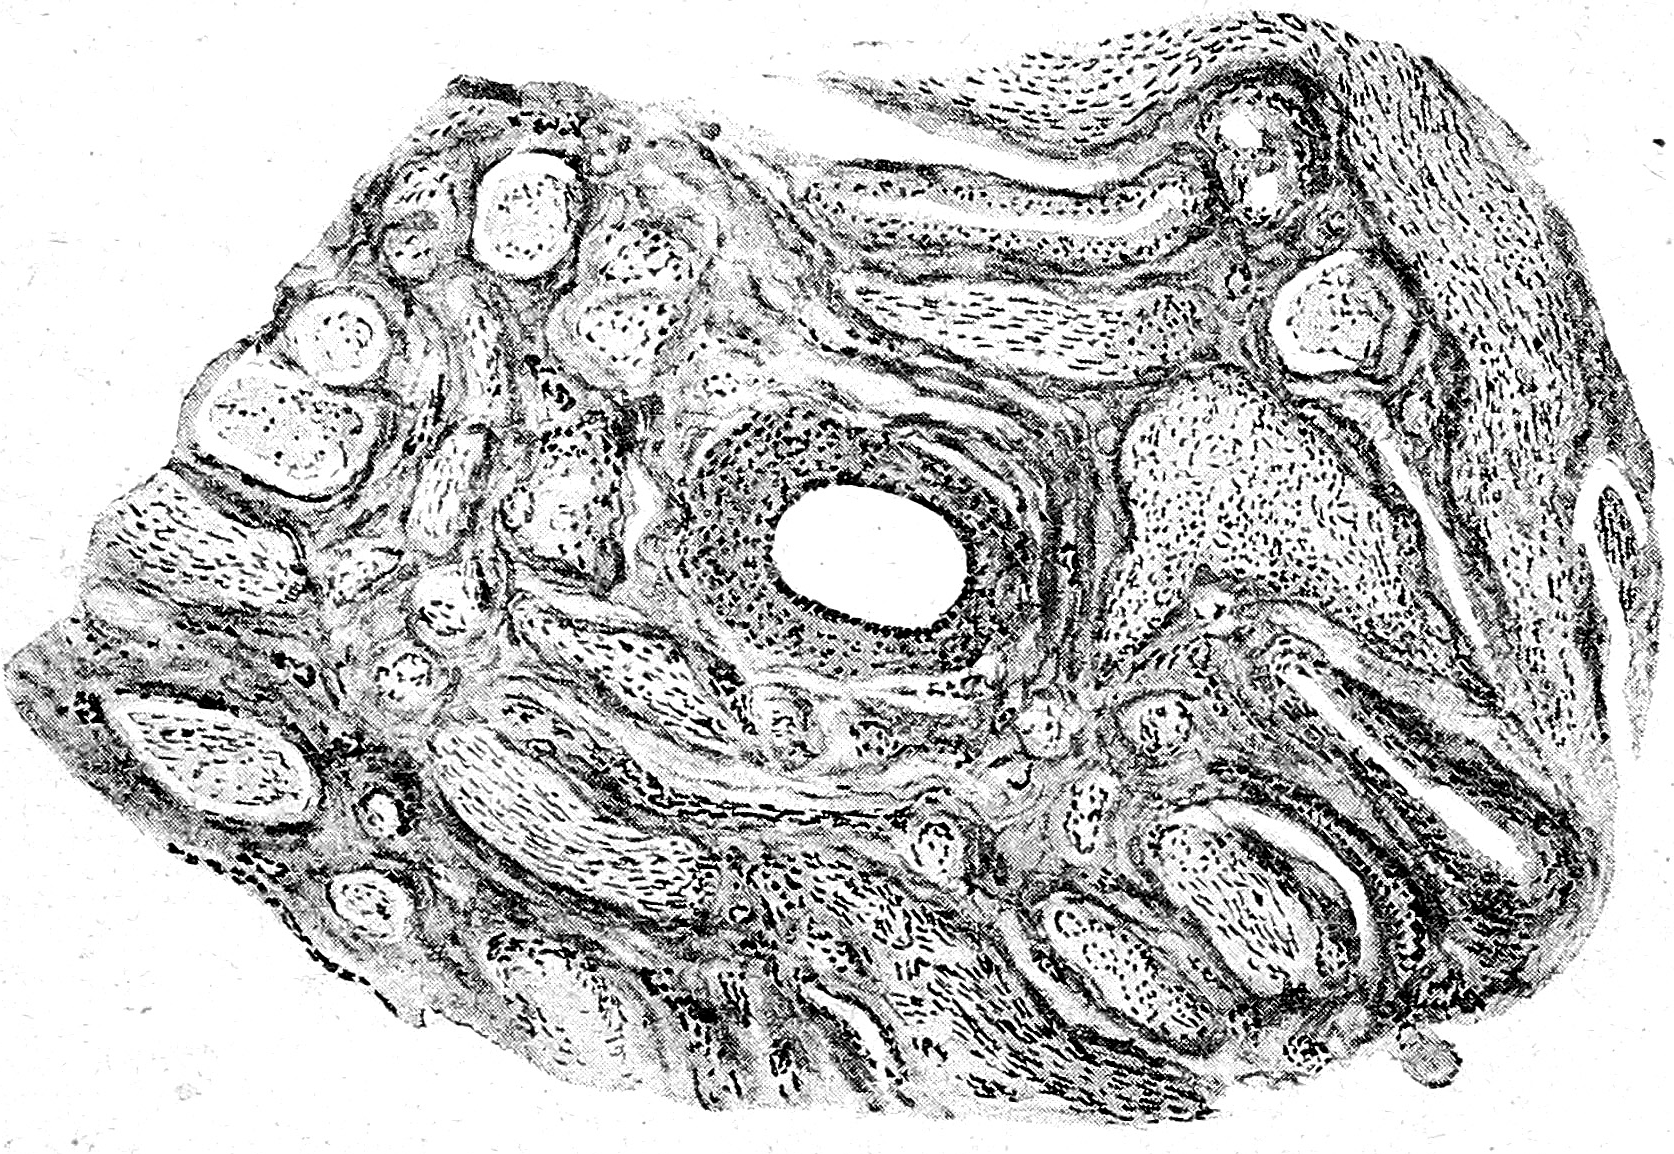

Операция. 22/VI, под хлороформным наркозом, д-ром Б. П. Енохиным совместно со мною была произведена herniotomia. Разрез 4,5 стм. походу пахового канала до апоневроза m. obliqui externi; последний рассечен; кровоточащие сосуды захвачены зажимами, после чего тупым путем выделен грыжевой мешок. В последнем прощупывалось неправильно-овальной формы, подвижное тело, при давлении не уменьшавшееся, макроскопически похожее на яичко, а непосредственно с ним было соединено другое, меньшее по общему и более мягкое тело,—по-видимому, придаток яичка, далее же—-плотный тяж и какое-то утолщение, шедшее в брюшную полость. По вскрытии грыжевого мешка вытекло немного прозрачной светло-желтой жидкости, и тотчас же из мешка выступило яичко с придатком; а. при вытягивании последних показалось образование, напоминавшее матку с левым яичником и яйцеводом (рис. 1); все это образование было покрыто и прикреплено к малому тазу при помощи широкой пластинки брюшины (Lig. latum). Яичко с придатком и vas leferens были зажаты клеммами и отсечены от упомянутого сейчас образования, сосуды перевязаны, образовавшийся при этом дефект брюшины зашит наглухо. После того было удалено образование, напоминавшее женскую половую железу с маткой и яйцеводом, а яичко надрезано, причем на разрезе видна была нормальная строма его, то-есть tunica albuginea, от которой кнутри радиально шли septulae testis, делившие паренхиму яичка на дольки сероватого цвета. Надрез яичка был потом зашит, образовавшаяся культя С мужскими внутренними половыми органами погружена в грыжевой мешок, последний наглухо зашит и опущен через паховое кольцо в брюшную полость. В заключение был наложены швы на апоневроз и кожу. Послеоперационный период протек, вполне нормально. Через 7 дней швы были сняты. Операция иная рана зажила per рrіmаm intentionem и больной выписался 3/ѴІІ.

Рис. 1.

Уже макроскопически извлеченное из грыжевого мешка и удаленное образование напоминало, как уже упоминалось выше, внутренние женские половые органы. Утолщенная часть его, которая прилегала к яичку с придатком, напоминала рудиментарную матку, а от нее влево шла Fаllорі’eва труба в 28 мм. длиною, которая, как и в норме, к периферии расширялась и оканчивалась ясно выраженными фимбриями. У наружного конца трубы имелась сидевшая на ножке Моrgagni’eвa гидатида. Ниже яйцевода на обычном мосте, то-есть на задней поверхности широкой связки, располагалось тело, походившее на яичник,—продолговатое, с поверхности гладкое, в 12 мм. длиною, при наибольшей ширине в 5 мм. и толщине в 2.5 мм. От матки к яичнику тянулся соединительно-тканнный тяж lig. ovarii proprium. В mesosalpinx’е, при рассматривании его на свет, ясно различалась сильно развитая сеть канальцев epoophoron’a. По передней поверхности удаленного образования, в толще брюшины от места соединения собственной связки яичника с дном матки про бегал тяж по направлению кнаружи и вниз в паховую область,— круглая маточная связка.